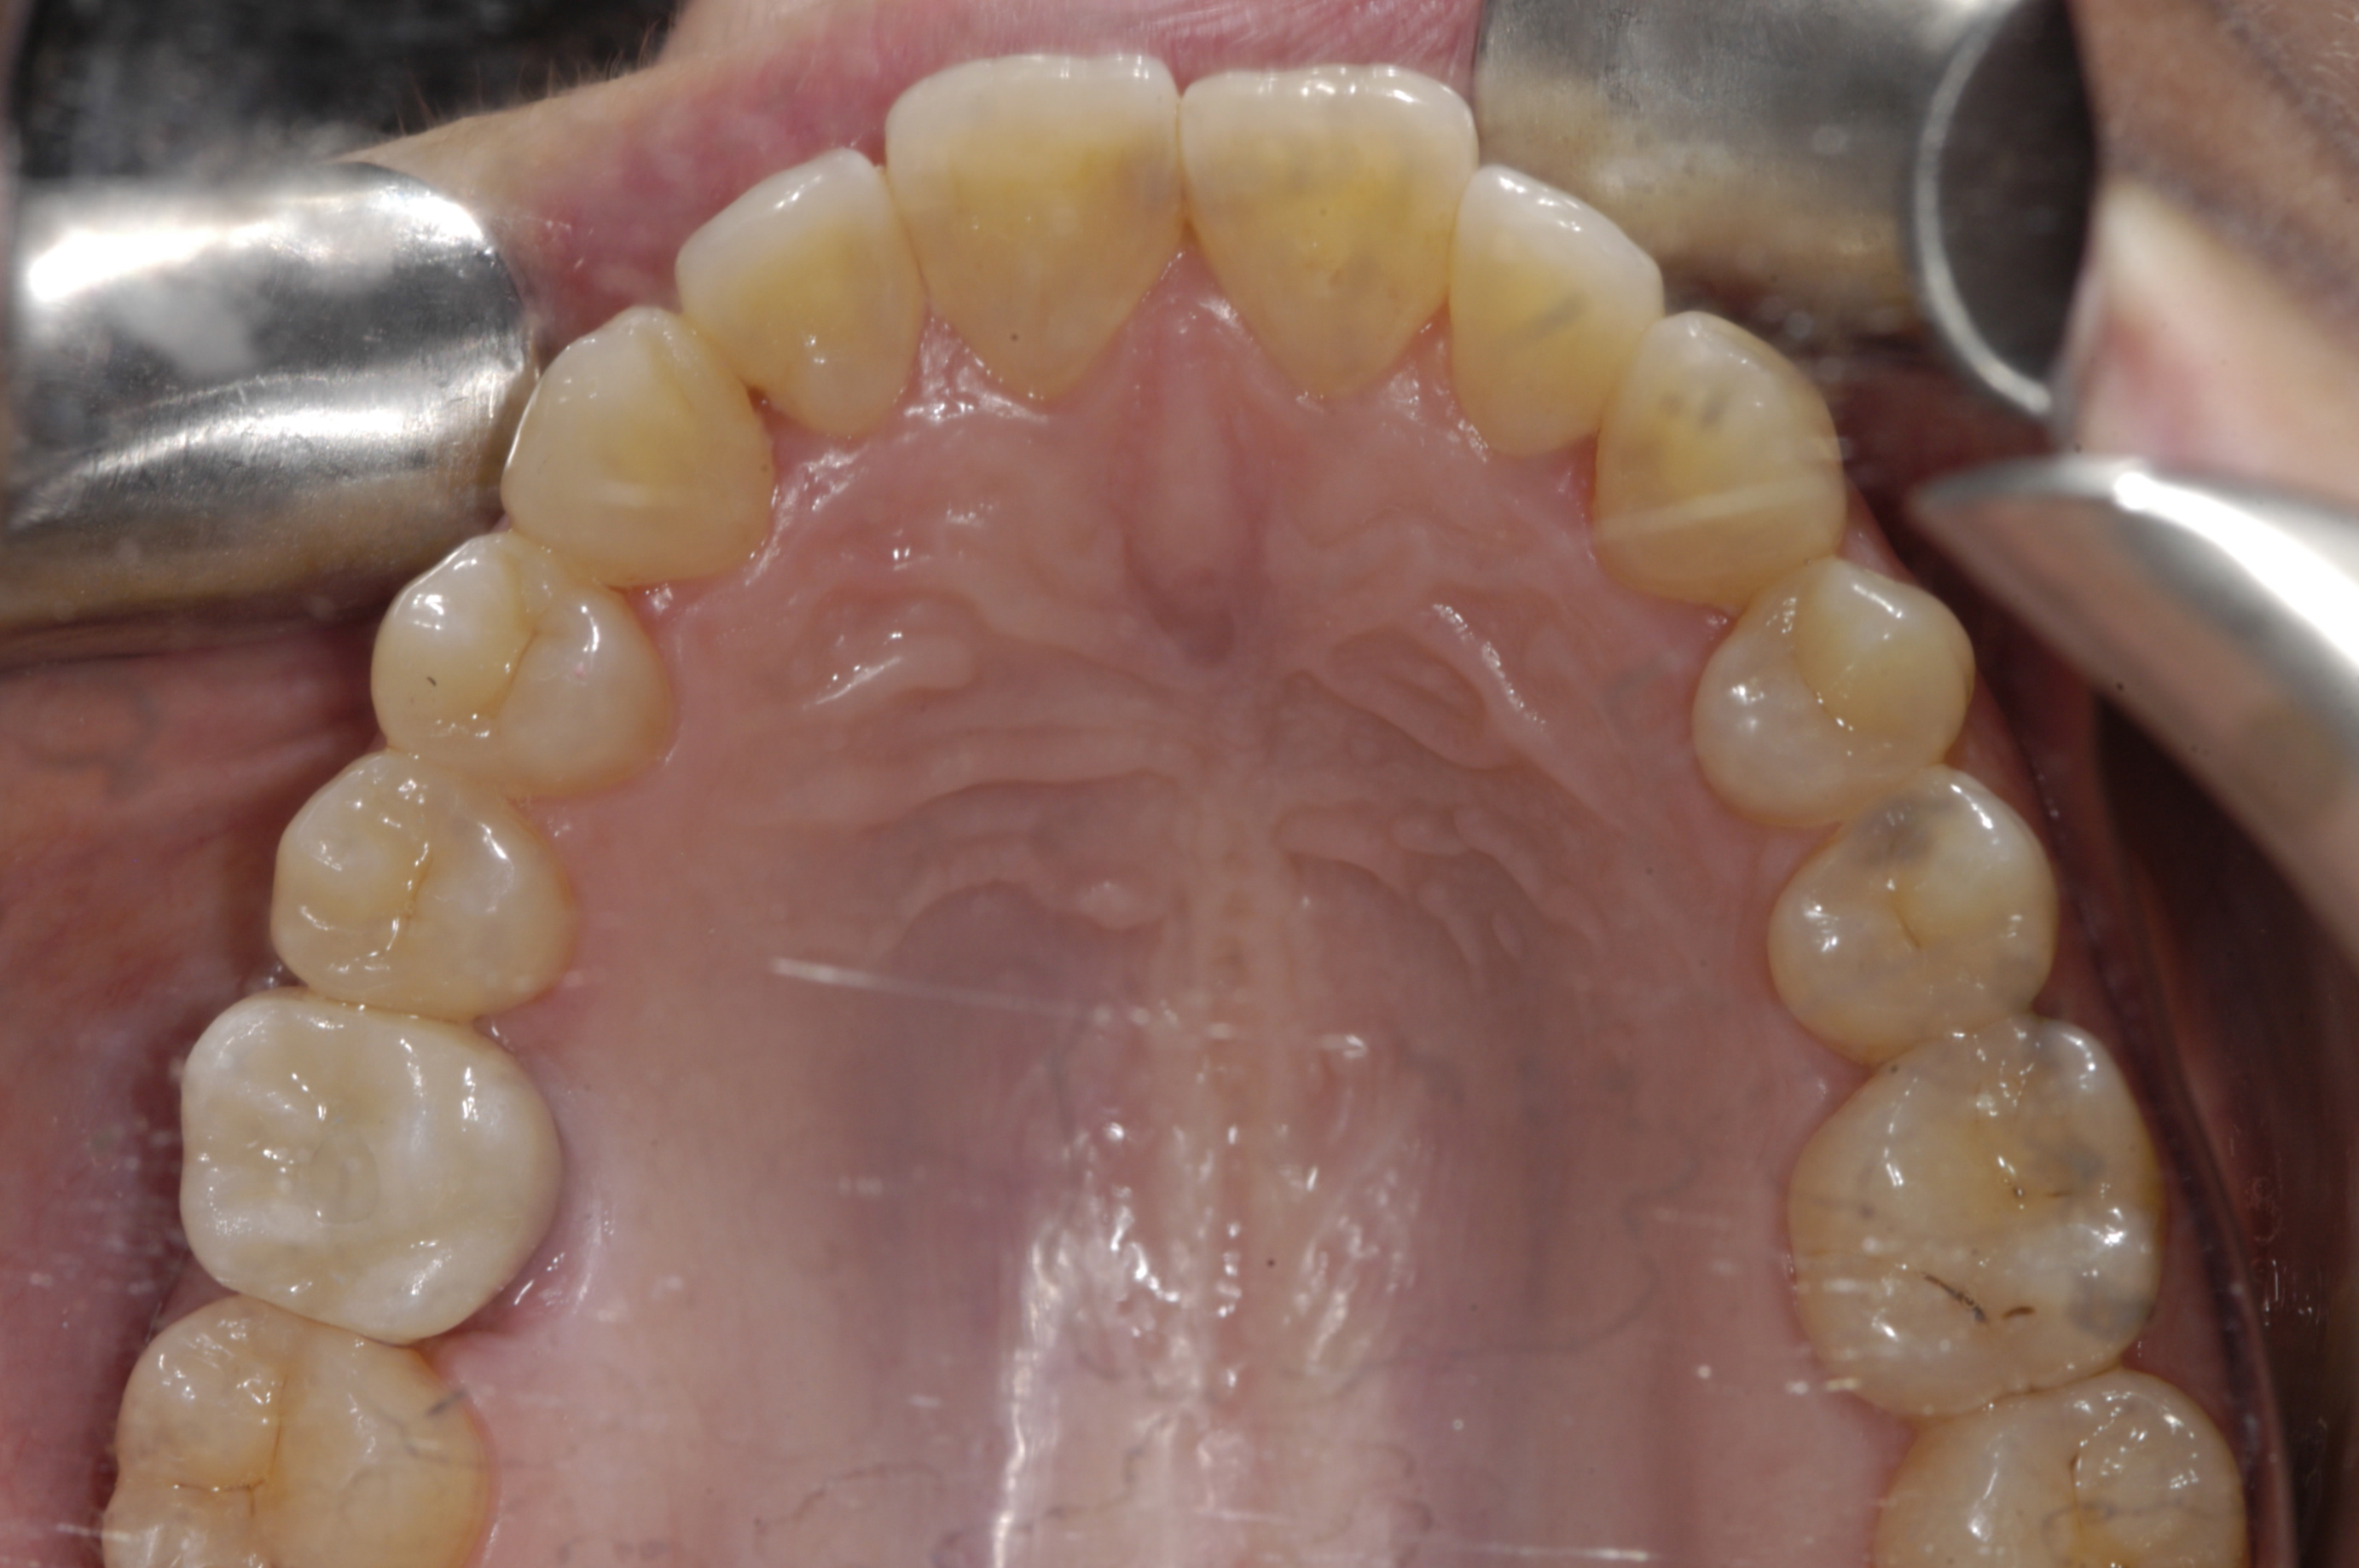

The first step is to design the desired restoration. If designed with CAD/CAM design software (Figure 1), the restoration will need to be saved in a file type that is compatible with the implant-planning software being used. If using an analog wax-up, the waxed up model will have to be scanned with either a laboratory scanner or a chairside CAD/CAM scanner and saved in a compatible file type.

Digitally designed restoration for an edentulous space.

Figure 1